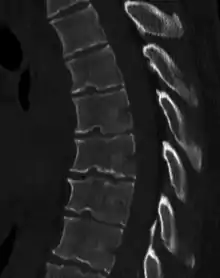

| Scheuermann's disease on lateral Xray of the T spine | |

Scheuermann's disease is a self-limiting skeletal disorder of childhood. Scheuermann's disease describes a condition where the vertebrae grow unevenly with respect to the sagittal plane; that is, the posterior angle is often greater than the anterior. This uneven growth results in the signature "wedging" shape of the vertebrae, causing kyphosis. It is named after Danish surgeon Holger Scheuermann.[3][4][5]

Diagnosis is typically by medical imaging. The degree of kyphosis can be measured by Cobb's angle and sagittal balance.